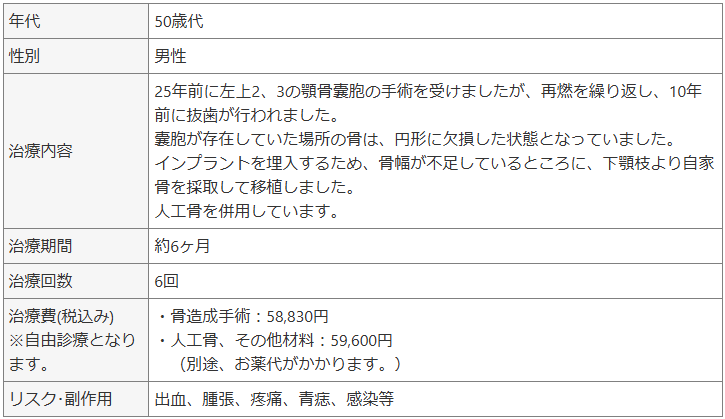

症例③ 上顎前歯部の歯槽骨欠損に対してブロック骨移植を行なった治療例。